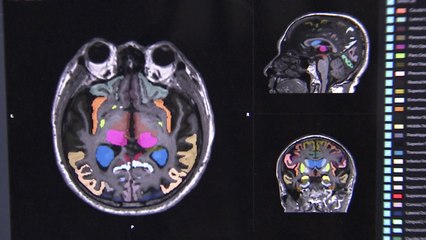

[앵커] 알츠하이머 치매는 현대인의 10대 사망원인 가운데 유일하게 예방이나 치료법이 없습니다. 그런데 국내 연구진이 물에 타 먹으면 알츠하이...